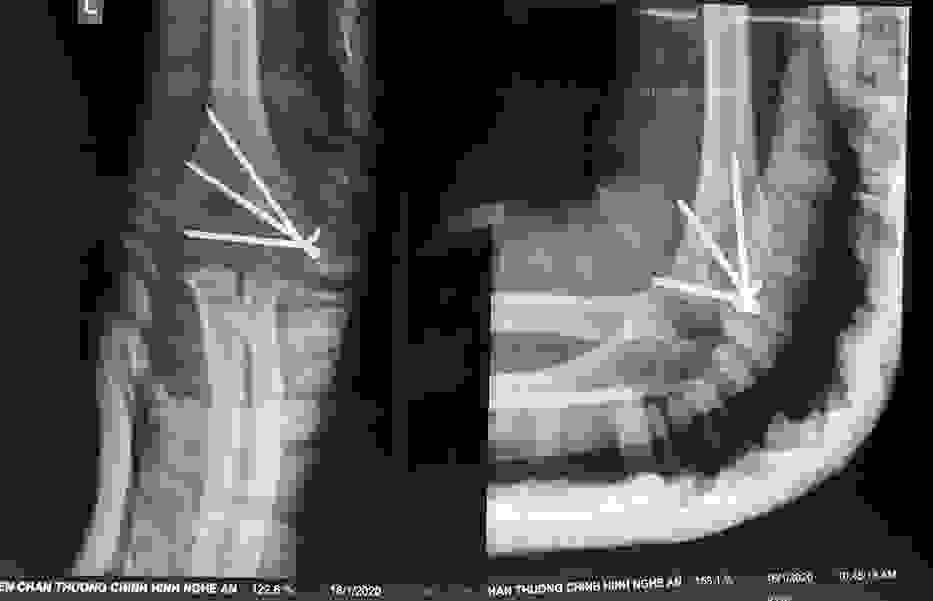

Điều trị gãy lồi cầu ngoài xương cánh tay ở trẻ em

12/03/2020 17:00

Đã xem: 5534